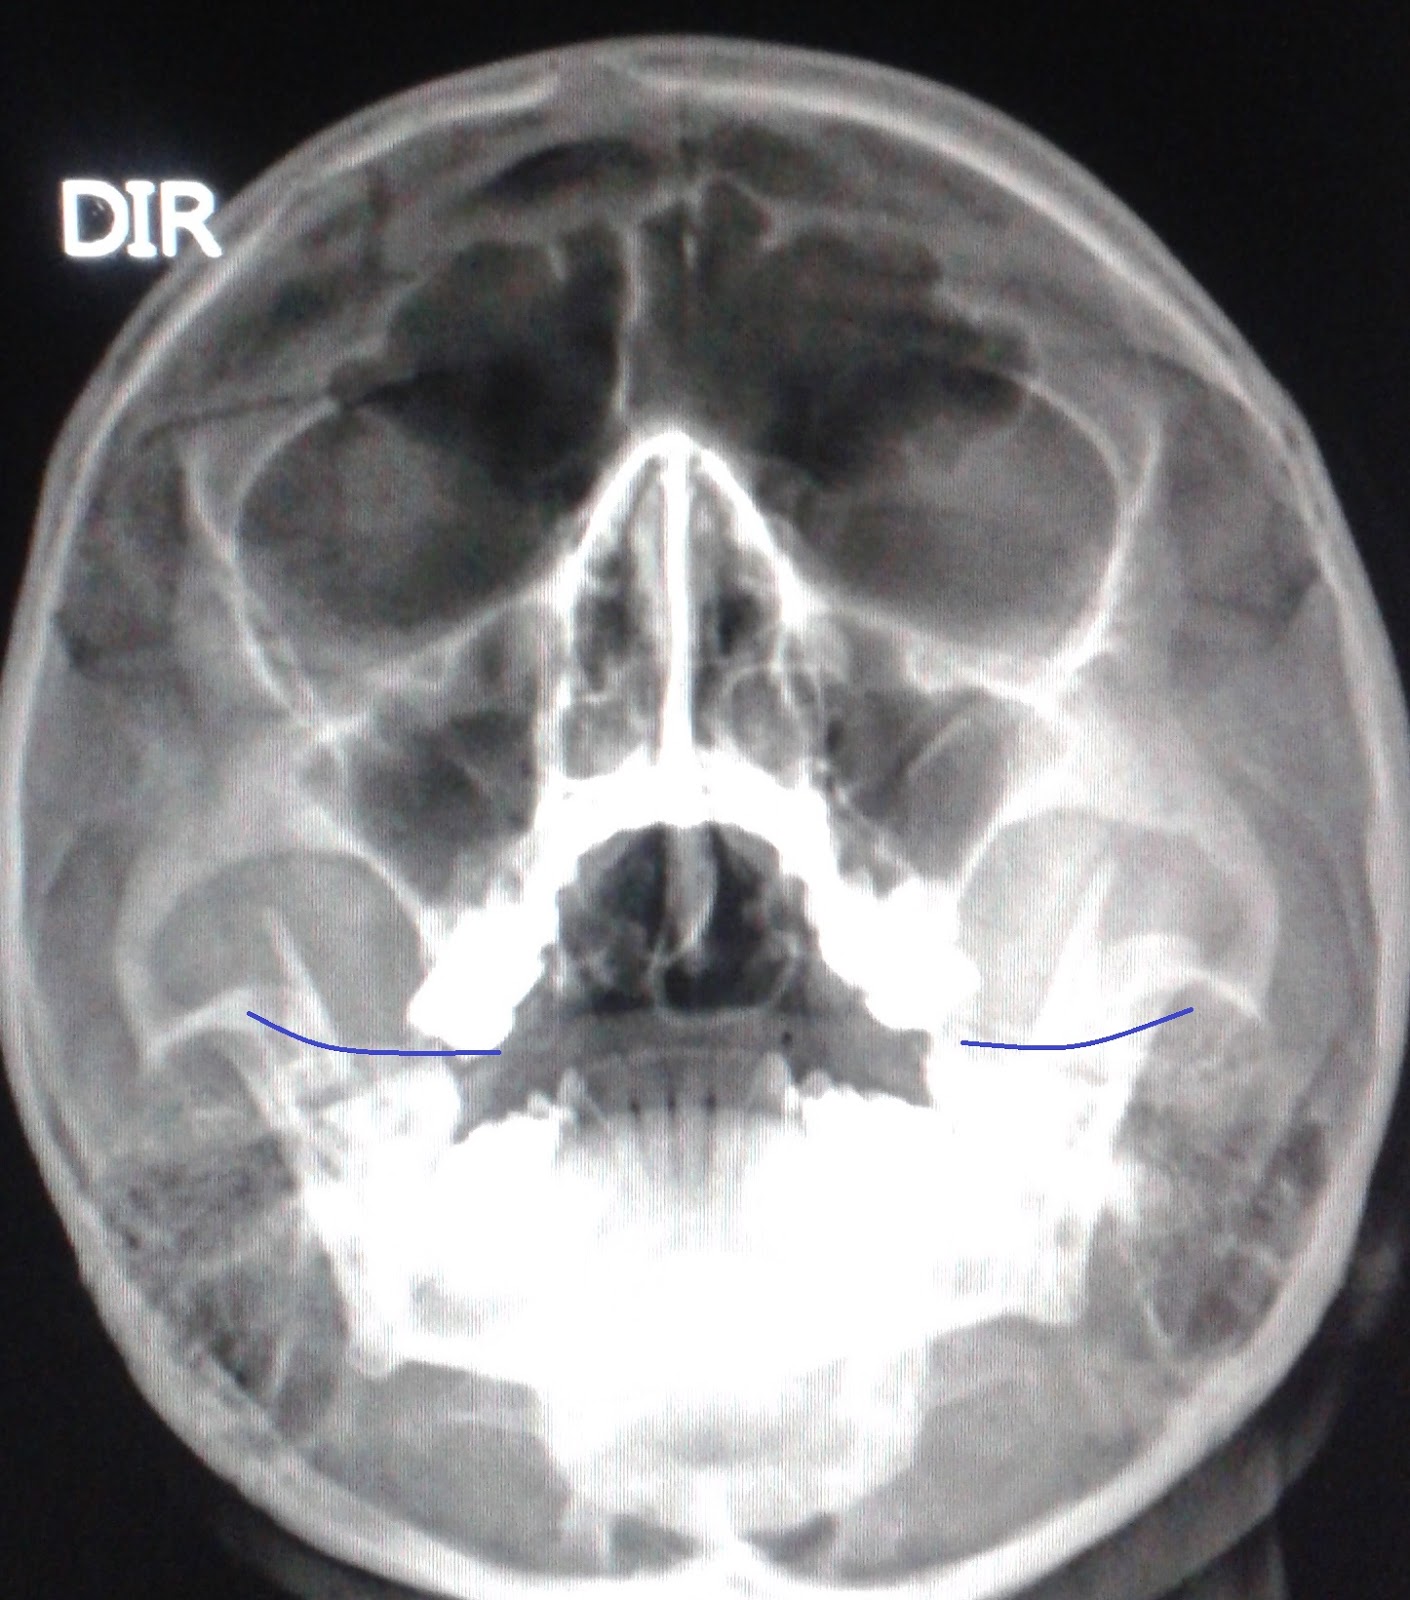

DICAS DE RADIOLOGIA: COMO AVALIAR A QUALIDADE DA RADIOGRAFIA DE SEIOS

Source: dicasradiologia.blogspot.com

WebSinais de sinusite na radiografia dos seios da face - YouTube Sinais de sinusite na radiografia dos seios da face Sinais de sinusite na radiografia dos seios da. WebUma radiografia ou raio X dos seios perinasais é um exame de diagnóstico por imagem que emprega radiação X, possibilitando avaliar esta estrutura anatómica e, desta.